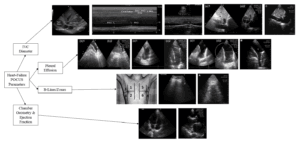

Using the “Abdominal” preset, the IVC was assessed at end-expiration. The diameter was measured 2 cm away from the hepatic vein entrance. Images and measures were performed in long and short axes to avoid errors. The mean value of two measures was reported. The portal vein was assessed at end-expiration, with no more than 30° for pulsed-wave Doppler interrogation. The pulsatility index was considered positive when its value was equal to or above 30% pulsatility. Measures and techniques for portal vein evaluation were the same as those used for the VExUS score protocol (Figure 1) [6].

Figure 1. Point of care ultrasound (POCUS) evaluation of congestion. A. Portal vein pulsatility evaluated in the hepatic window with a pulsed wave Doppler. A1. Portal vein pulsatility less than 30%. A2. Portal vein pulsatility above 30%. B. Lung ultrasound. B1. A-lines in a lung without congestion. B2. B-lines in the context of Alveolar interstitial syndrome. C. Lung ultrasound for the evaluation of pleural effusion. C1. No pleural effusion. C2. Pleural effusion in the right lung.